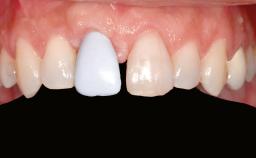

A 47-year-old Caucasian woman with a single-tooth edentulous space at the site of the left maxillary canine was referred for treatment. She had undergone traumatic extraction of this impacted canine several months before referral. Her chief complaint was the dissatisfying appearance of her smile. The patient desired a stable and esthetic rehabilitation of the site. Her dental history showed no evidence of periodontal disease or bruxism. She had no systemic diseases, was not taking any medications, and did not smoke. The extraoral examination revealed a high lip line and an inadequate soft-tissue volume at the defective canine site. Large black triangles were visible between the canine and its adjacent teeth.

Soft Tissue Anatomy Intact Defective

Bone Volume Horizontally and vertically sufficient Horizontally deficient Deficient vertically or deficient vertically AND horizontally